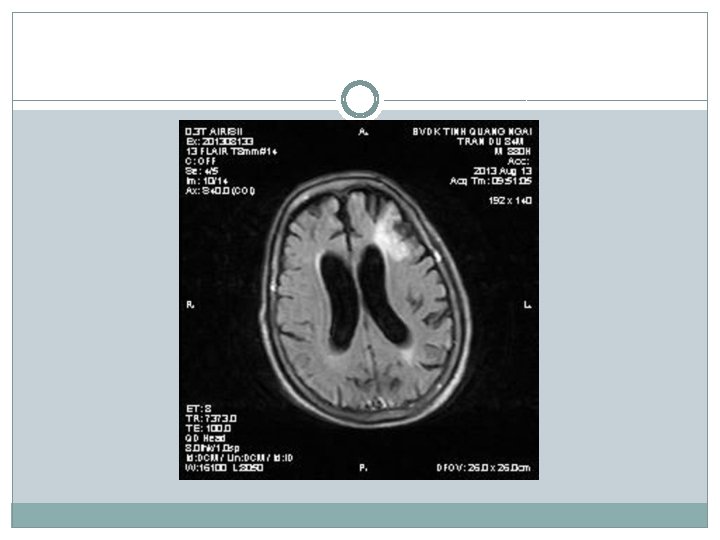

�Siêu âm có nang thận phải # 34 mm �X-quang tim phổi bình thường; thoái hóa cột sống thắt lưng �Điện não: chủ yếu sóng chậm Theta, ưu thế vùng trán (T) �Điện tim bình thường �CT scan não: Nhồi máu não thùy trán (T) �MRI não: Nhồi máu thùy trán (T), teo vỏ não thùy trán + não thất giãn nhẹ

Chẩn đoán �Tuy nhiên có điểm chưa phù hợp trong chẩn đoán bệnh Parkinson: khởi bệnh run cả hai bên đối xứng; hình ảnh học MRI cho thấy có teo vỏ não, có biểu hiện rối loạn tâm thần sớm